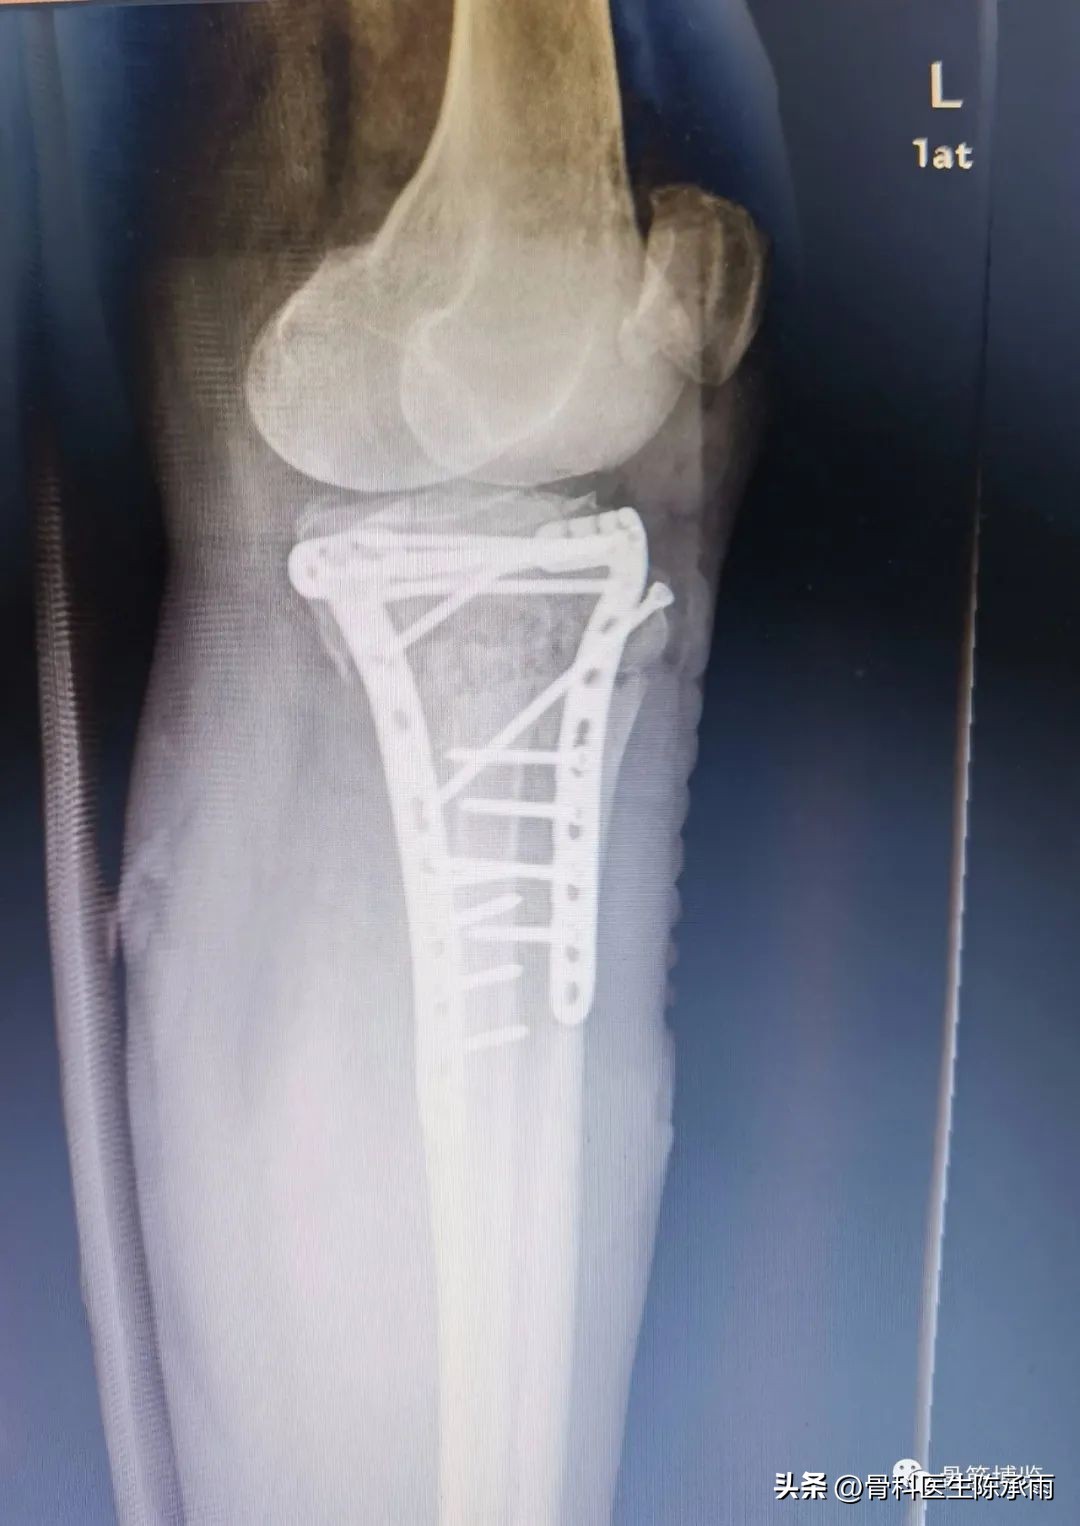

1例

2例

3例

4例

5例

6例

7例